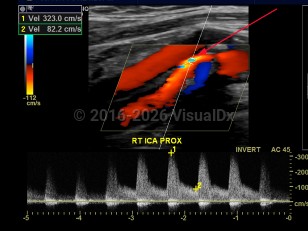

Carotid artery stenosisCarotid artery stenosis